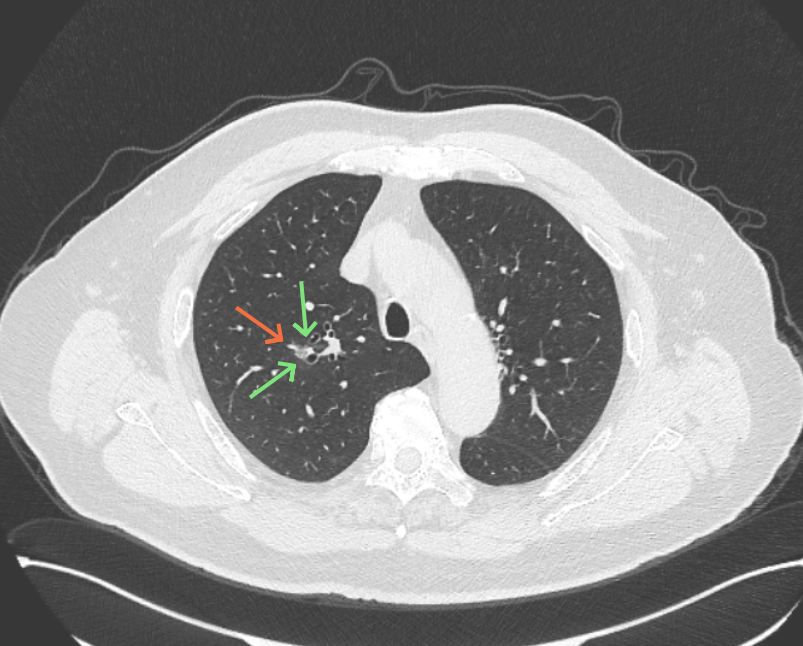

病灶没有确切纵隔窗可见的实性成分,但与血管关系较为密切。

再看2026年3月最近复查时不同层面病灶A的细节影像特征:

微小血管走向病灶,磨玻璃的密度淡而较纯。